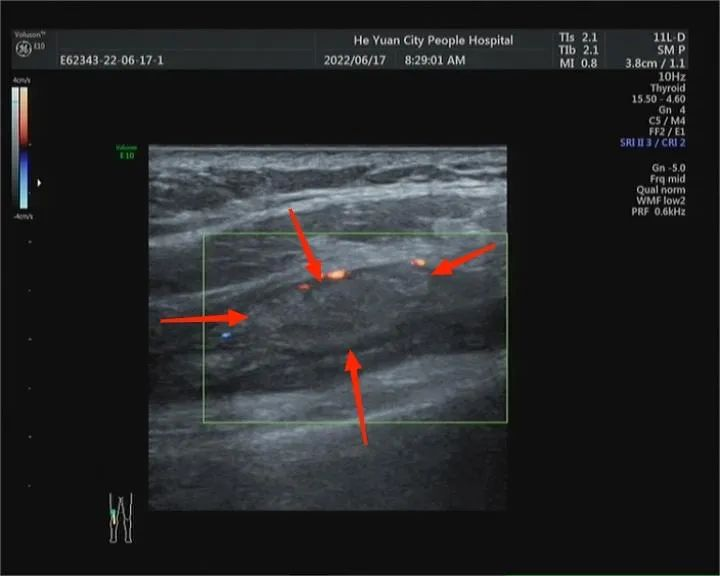

2、关节周围包块

检查是否存在代谢类或占位性病变等。常见的代谢类疾病包括痛风石、类风湿关节炎等;常见的占位性病变包括腱鞘囊肿、软组织肿瘤等。

痛风石